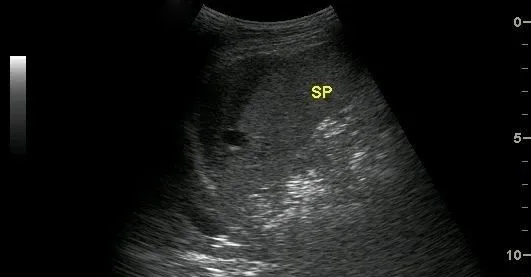

根據脾破裂的部位臨床將其分為三種類型,即包膜下血腫、中央型脾破裂及真性脾破裂,各型脾破裂的損傷部位及超聲表現如下:

中央型脾破裂

是指脾臟實質內部的出血,在脾臟內形成血腫。

超聲表現為:脾臟實質內探及邊界清楚的非均質區,單發或多發,如伴有較大血腫時,非均質區內可探及不規則或類圓形無回聲區,透聲較差。